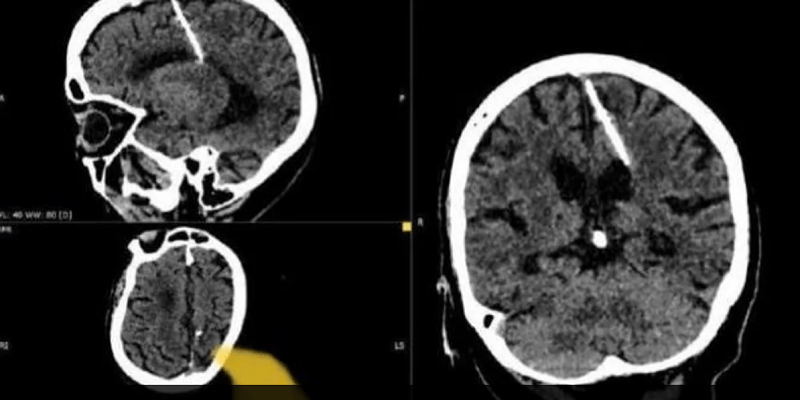

في إحدى الدول في أقصى الشرق الروسي عثر أطباء خلال فحص بالتصوير المقطعي على إبرة بطول ثلاثة سنتيمترات موجودة منذ ثمانين عامًا داخل دماغ امرأة مسنّة.

وأكد الأطباء بأنهم لن يحاولوا إزالة تلك الإبرة وذلك خشية من أن يفاقم ذلك من حالتها.

ومن جانبها، قالت إدارة الصحة المحلية: “لقد اخترقت الإبرة الفص الجداري الأيسر، لكن لم يكن لها التأثير المقصود، إذ نجت الفتاة”

وأوضحت أن المريضة لم تشكُ أبدأ من الصداع بسبب الإصابة، ولم تكن تواجه أي خطر. مؤكدة أن حالتها تحت المراقبة.